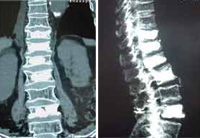

![]() El Dr. Morgenstern realizando una Cifoplastia |